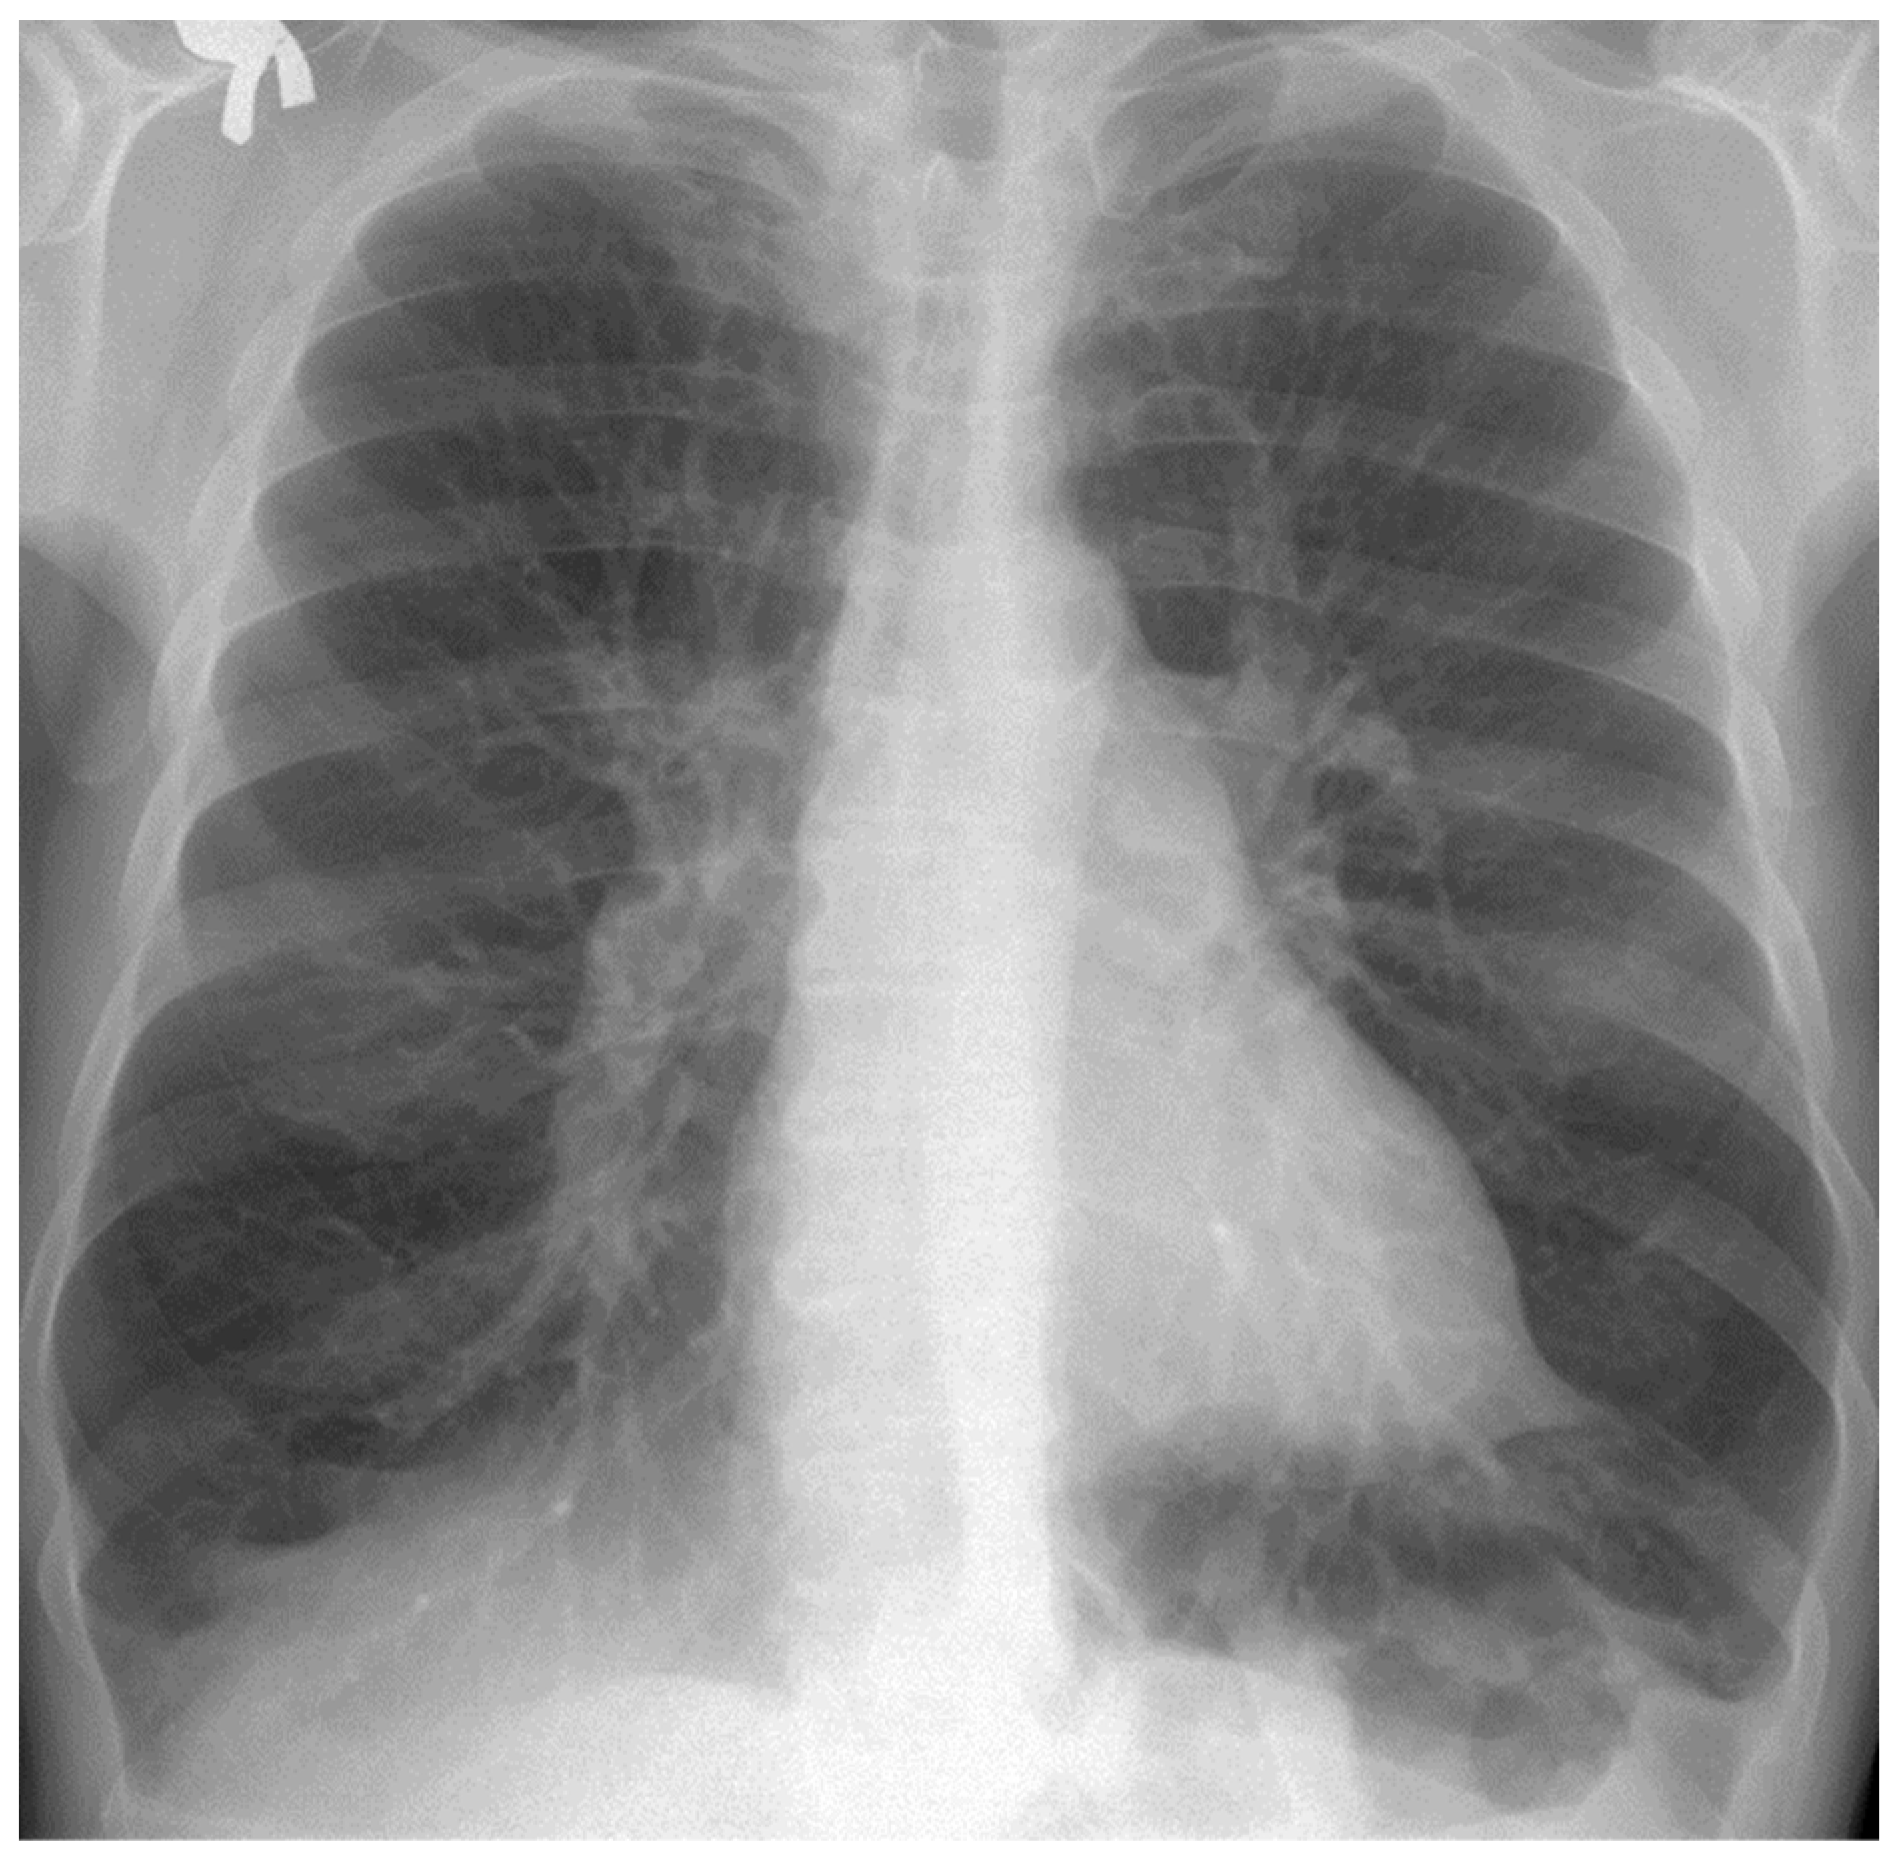

The chest radiograph of healthy lungs on which the fractal analysis was performed is shown in Figure 29a. Aside from the high-quality imaging provided by CT procedures (Figure 29a,b), the picture evaluation assured quantitative information regarding various structural features, such as the fractal dimension and lacunarity.

Figure 30 shows the 2D box-counting algorithm with the local fractal dimension calculation for the healthy-lung CT image. Figure 31 displays the 3D graphical representation of the voxels present in the CT lung image of healthy patient. Table 7 presents the calculated values for the fractal dimension and the lacunarity of the CT image evaluations for the healthy patient.

Table 7 shows the known fractal indicators, such as the fractal dimension of the CT image of the left lung, dHL = 1.6410 ± 0.3577, and lacunarity Λ = 0.0475; and the fractal dimension of the right lung, dHR = 1.6318 ± 0.3598, and lacunarity, Λ = 0.0486.

Figure 29. (a) Healthy lung image, (b) binary version, (c) mask for the left lung, (d) mask for the right lung.